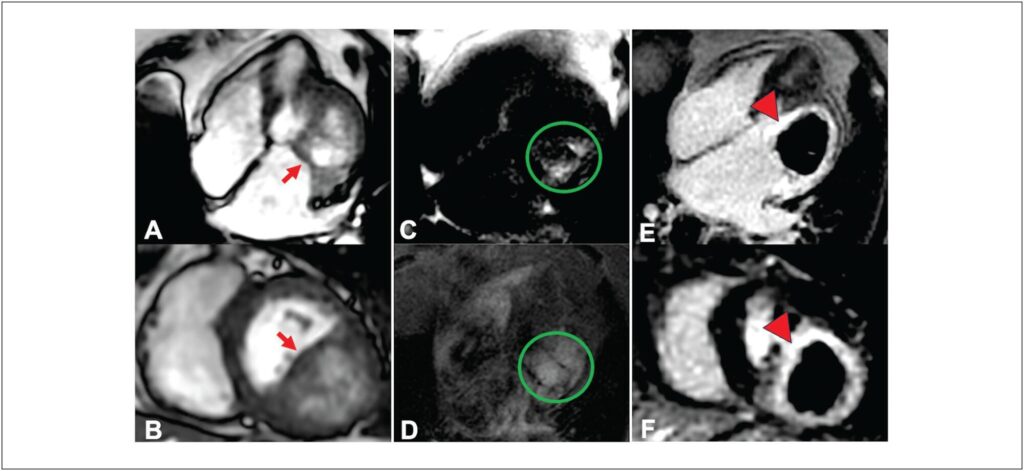

Massas cardíacas, embora raras, podem levar a problemas hemodinâmicos e arrítmicos importantes, mesmo quando benignas. O avanço do exame multimodal refinou o diagnóstico e o entendimento dessas massas. Apresentamos um caso de uma mulher de 85 anos, com dispneia classe II-III (New York Heart Association) há seis meses. O ecocardiograma mostrou uma massa na parede ínfero-lateral basal do ventrículo esquerdo, dilatação grave do átrio esquerdo, e regurgitação mitral moderada. A primeira hipótese era cisto pericárdico, mas o exame de ressonância magnética cardíaca (RMC) revelou uma massa intramiocárdica, e a tomografia computadorizada (TC) sugeriu um cisto hidático. Dados os sintomas não limitantes e o alto risco cirúrgico, decidiu-se pela vigilância ativa. Este caso ilustra a raridade dos cistos cardíacos e o papel essencial do exame multimodal no planejamento diagnóstico e terapêutico.